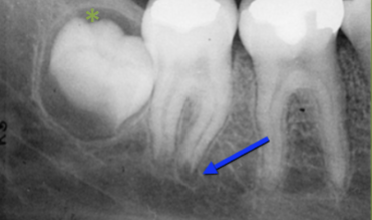

Assess the apical lucency at mesial root of 31

Normal Anatomy

Assess #32

Dentigerous Cyst

Evaluate #30

Widened PDL

Pulpal Disease

Evaluate #31

Normal PDL

Superimposed Anatomy

Notice other radiographic Features?